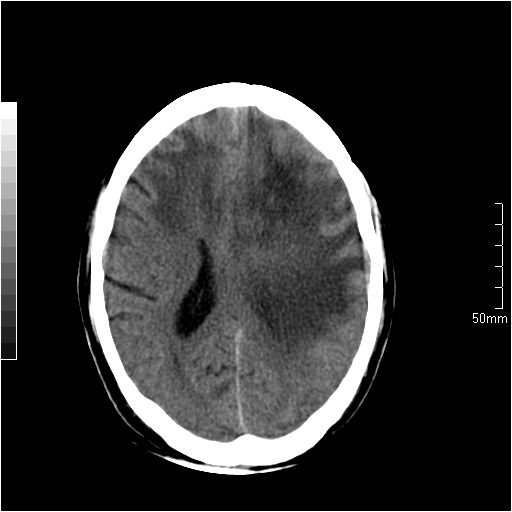

以下是引用天南地北在2007-6-25 12:39:00的发言:[br]有占位效应[br]支持术后复发

以下是引用zjzjr在2007-6-25 12:38:00的发言:[br]左侧复发,右侧转移。